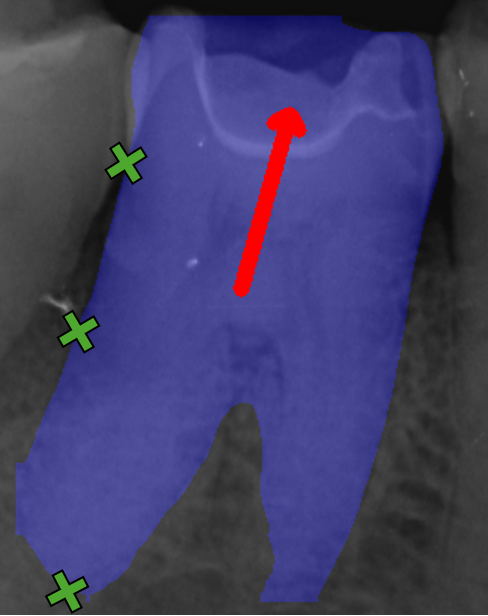

Disease Classification Metrics

To evaluate the models’ ability to detect clinically relevant stages of periodontal disease, we employ metrics that compare classification performance for conditions necessary to diagnose periodontal disease stages. To compute these metrics, we derive the Percentage of Bone Loss (PBL) using the CEJ, BL, and RL keypoints on both the distal and mesial sides of each annotated tooth. The BL and RL locations are projected along a straight line extending from the CEJ, oriented according to either the predicted rotation index or the target bounding box angle, as seen in Figure 6. We then calculate the percentage of bone loss for a specified tooth side as PBL=CEJBL¯2CEJRL¯2\text{PBL}=\frac{||CEJ-\overline{BL}||_{2}}{||CEJ-\overline{RL}||_{2}}, where CEJBL¯2||CEJ-\overline{BL}||_{2} is the Euclidean distance of the CEJ keypoint and projected BL keypoint, and CEJRL¯2||CEJ-\overline{RL}||_{2} is the Euclidean distance of the CEJ keypoint and projected RL keypoint.

Refer to caption

(a) Keypoints

(b) Projection

Figure 6: Cropped image of Image104.png, with example keypoint and projection process. Keypoints are represented as green crosses, projected points as green dots, the rotation index as a red arrow and the projection from CEJ as red lines.